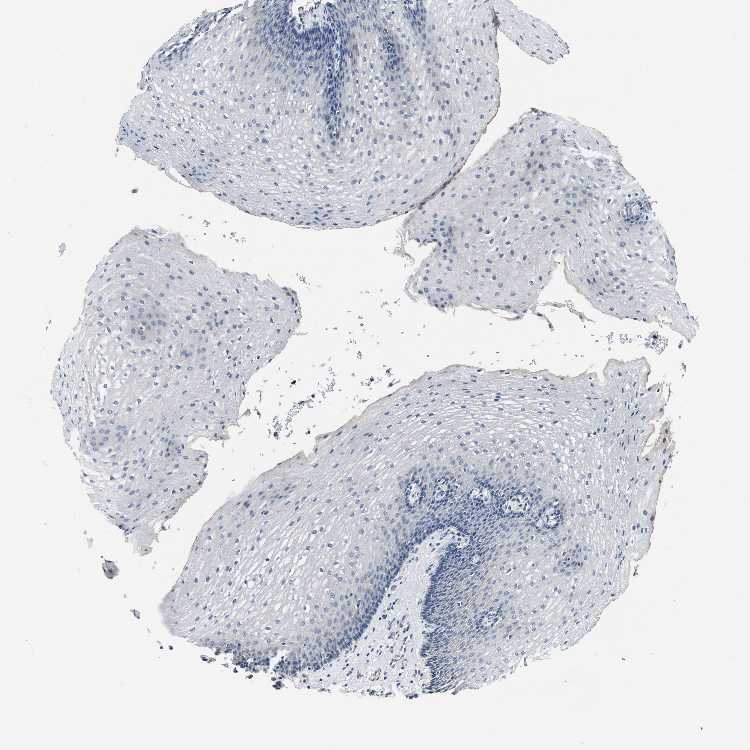

ESOPHAGUS - Antibody stainingi

Antibody staining in the annotated cell types in the current human tissue is reported as not detected, low, medium, or high, based on conventional immunohistochemistry profiling in selected tissues. This score is based on the combination of the staining intensity and fraction of stained cells.

Each image is clickable and will lead to virtual microscopy that enables deeper exploration of all samples and also displays staining intensity scores, fraction scores and subcellular localization as well as patient and tissue information for each sample.

Antibody HPA019711Antibody HPA029535

Squamous epithelial cells Not detectedLow